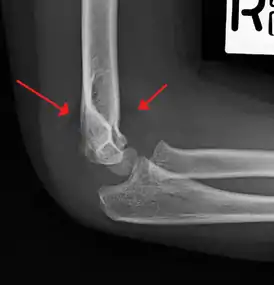

Fat pad sign/sail sign - A non-displaced fracture can be difficult to identify and a fracture line may not be visible on the X-rays. However, the presence of a joint effusion is helpful in identifying a non-displaced fracture. Bleeding from the fracture expands the joint capsule and is visualized on the lateral view as a darker area anteriorly and posteriorly, and is known as the sail sign.[8]

Anterior and posterior sail sign in a child who has a subtle supracondylar fracture